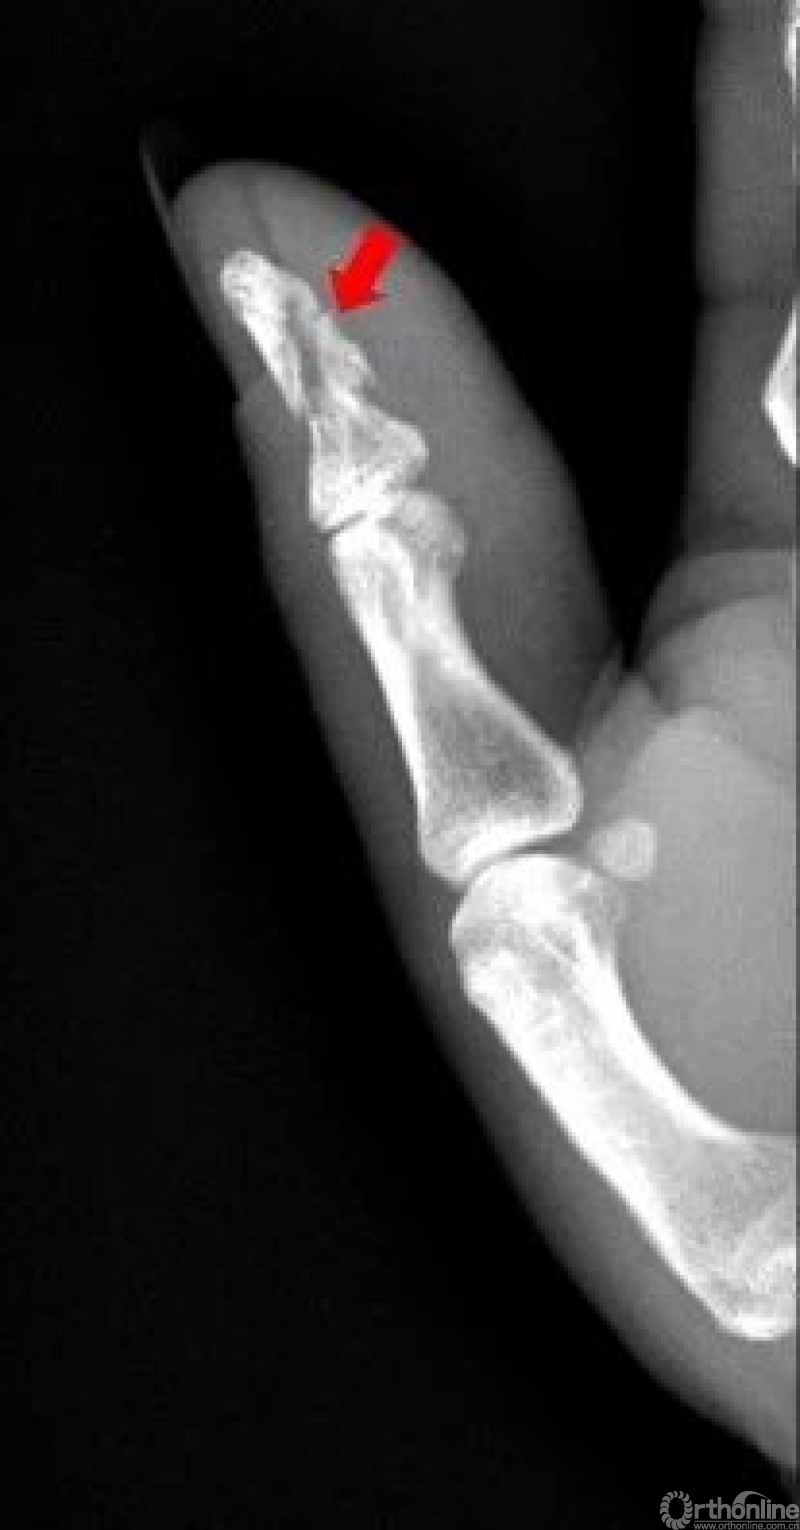

右手拇指近节远端见斜行骨折透亮线,断端稍分离移位,右手拇指近节远端骨折